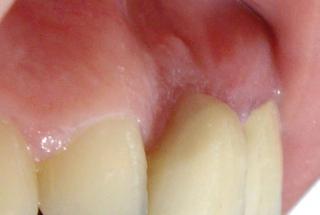

Clinical cases

MPI closely monitors clinical cases in the market to ensure their correct functioning and successful outcome.